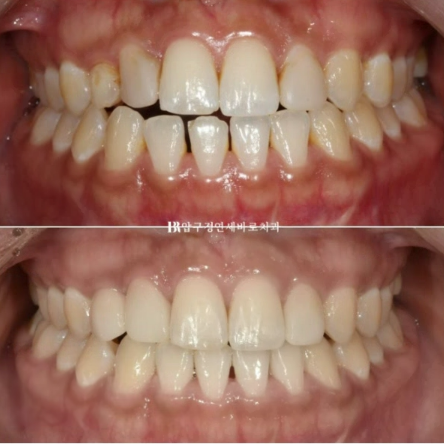

23.02~23.08